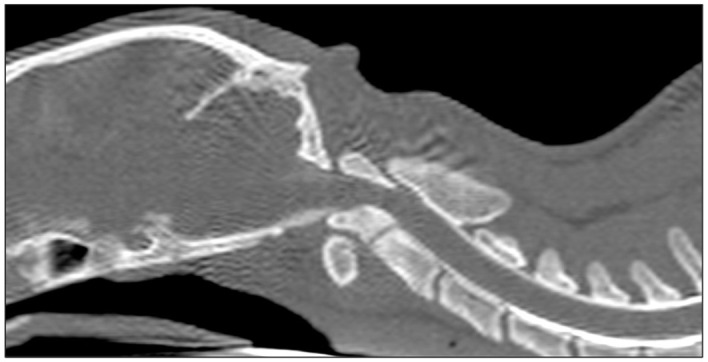

病例总结:本病例报告中描述的猫表现为进行性非活动性四肢全瘫。它被诊断为枕骨寰枢畸形(OAAM),导致严重的压缩性脊髓病。这种情况是由枕髁变平和椎体轴变短引起的。此外,在CT上观察到寰枢关节发育不良。这只猫接受了手术治疗,使用了一个板,这是在畸形的三维模型的帮助下定制的。手术后三周,这只猫能够在没有帮助的情况下行走;术后5年,猫的神经系统检查正常。相关性和新信息:使用三维技术的手术计划在复杂的OAAM病例中是有用的。这是第一个记录在案的猫科动物使用这种技术治疗这种疾病的病例。

Case summary: The cat described in this case report presented with progressive non-ambulatory tetraparesis. It was diagnosed with an occipitoatlantoaxial malformation (OAAM), which resulted in severe compressive myelopathy. This condition was caused by a flattening of the occipital condyles and shortening of the vertebral body of the axis. In addition, there was dysplasia in the atlantoaxial joint, which was observed on CT. The cat was treated surgically using a plate, which was custom-made with the help of a three-dimensional model of the malformation. Three weeks after surgery, the cat was able to walk without assistance; 5 years after surgery, the cat showed a normal neurological examination.